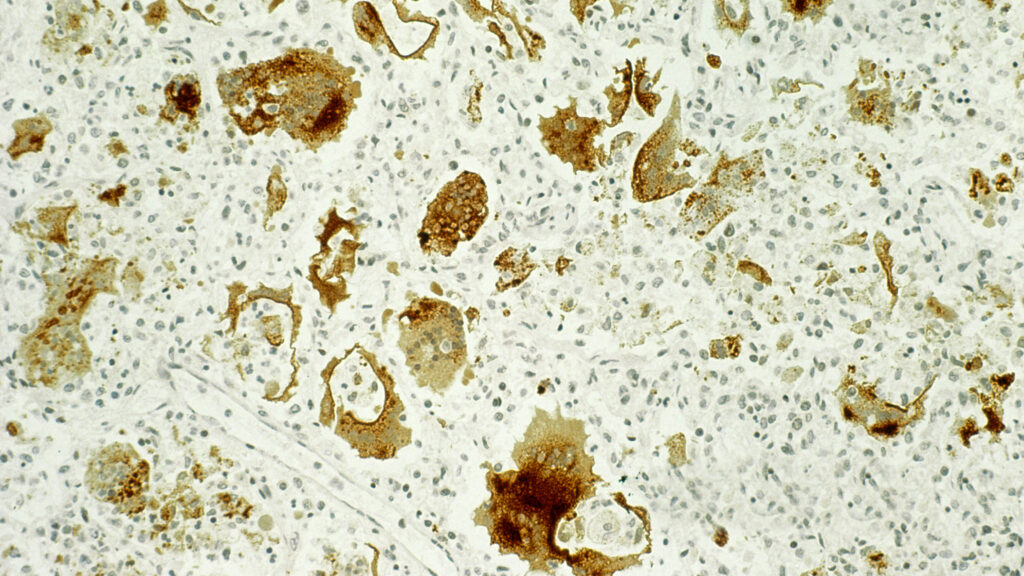

I recall the case of a healthy, thriving school-aged child who developed unexplained tremors, muscle weakness, and seizures. She had a serious complication of measles, subacute sclerosing panencephalitis, a rare and often deadly form of brain inflammation. When she was an infant, she lived in a country where the measles vaccine was not routinely given and became infected. Her mother was doing everything she could to care for her. Like measles, there is no treatment for subacute sclerosing panencephalitis. Over several months, her condition deteriorated, which was heart-wrenching for our entire medical team, especially in the last few months before she died. She was unable to walk, eat on her own, speak, or do other things we take for granted when we are healthy.

This 1966 photograph shows two public health technicians at a DeKalb County, Georgia, elementary school, vaccinating a young boy with two shots: a measles vaccine, and an immunity boosting, gamma globulin injection. CDC/ James J. CoxJames J. Cox/CDC

One of the first patients I saw as a pediatric intern (1972) was a boy around age 10 who had measles subsclerosing panencephalitis and was in a coma. He must have acquired measles prior to the vaccine availability around 1969, and he suffered this major neurological complication. He died sometime during my internship.